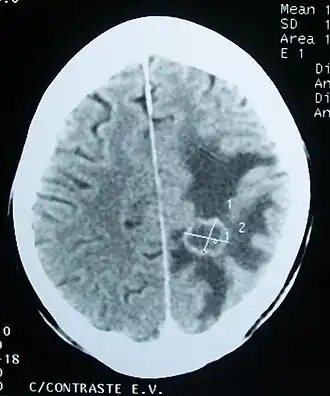

Œdème (zones sombres) autour d'une tumeur cérébrale secondaire.